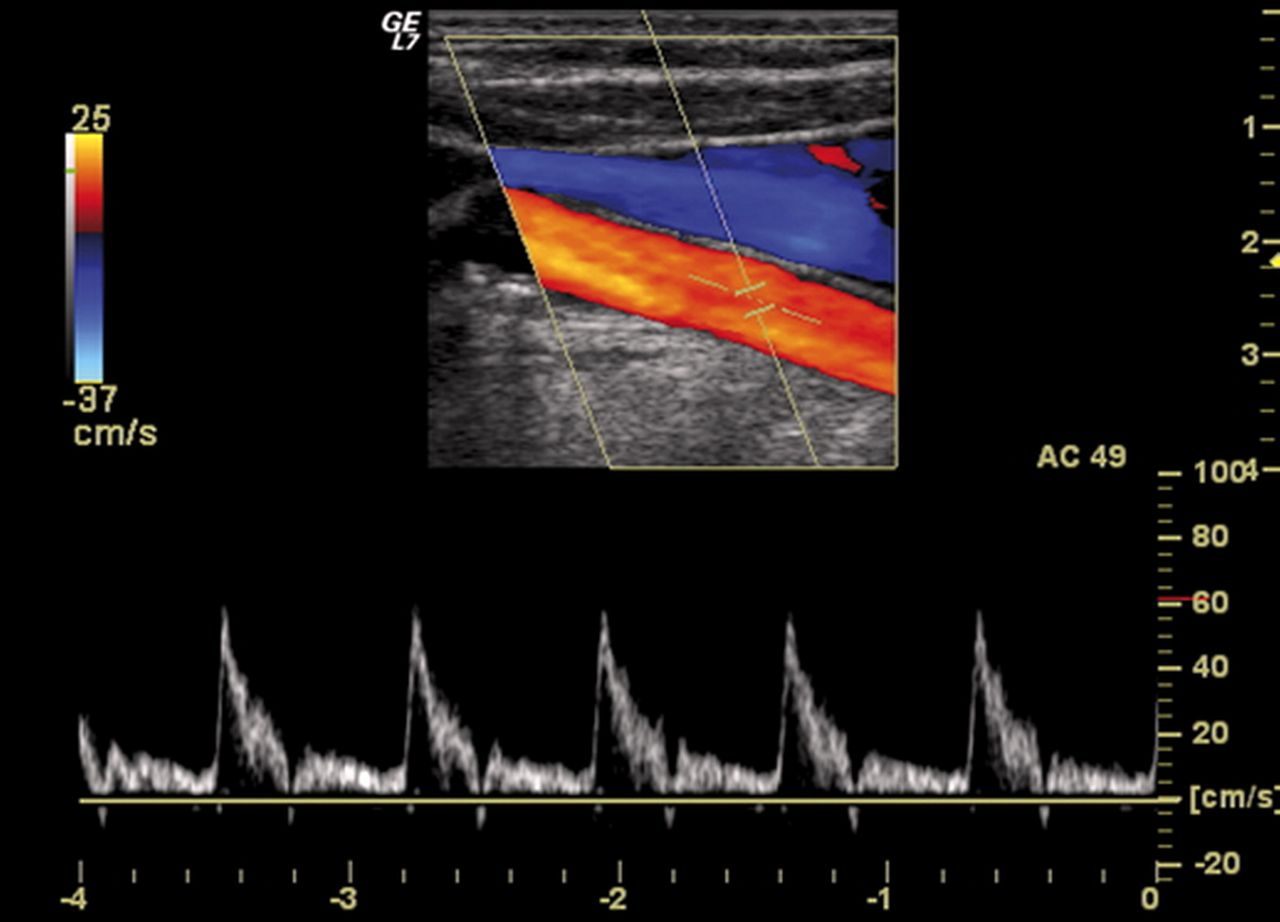

Tra gli esami diagnostici principali eseguiti dal chirurgo vascolare vi sono l’ecocolordoppler venoso e l’ecocolordoppler arterioso. L’ecocolordoppler venoso valuta il flusso sanguigno nelle vene, utile per identificare trombosi e insufficienza venosa. L’ecocolordoppler arterioso esamina le arterie per rilevare stenosi, occlusioni e aneurismi. Questi esami non invasivi combinano l’ecografia con la tecnologia Doppler per fornire dati dettagliati e informazioni sul flusso sanguigno, essenziali per una diagnosi accurata e un trattamento efficace.